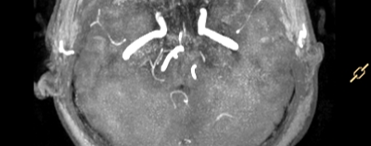

The plain scan report indicates: high signal in the white matter (Fazekas grade I), suspicious low signal in the right cerebellar hemisphere on T2WI with abnormal ADC signal, further examination is recommended; TOF-MRA suggests slight narrowing of the left anterior cerebral artery A1 segment;Therefore, an MRI enhancement scan was additionally ordered; after the examination, no obvious abnormal enhancement was observed, with results as shown in the images:

After completing the examination, the diagnosis and clinical team felt confused about the results; thus, they consulted the author regarding the cause.2. Cause Analysis1.Reasons and Identification of Abnormal Image InformationThe issue was discovered during the plain scan, so we must first look at the images: from the ADC map, we can see significant diffusion restriction in the right cerebellar hemisphere; however, upon reviewing other weighted images, no corresponding abnormalities were found in that area. Where does the description of low signal on T2WI in the report come from? Upon reviewing the report description, I found that “no abnormal high signal was seen in the DWI sequence, and low signal was observed in the right cerebellar hemisphere on b=0 and ADC map with chaotic tubular and patchy low signals”; combined with the actual image performance, we can infer that the report physician’s description of the abnormal T2WI signal was based on the B0 image.As we know, the B0 image of the DWI sequence is equivalent to a T2 star fat-suppressed weighted comparison, which is more sensitive to the Mxy phase acceleration loss caused by B0 field inhomogeneity and is often used to assist in judging fat signals or ferromagnetic substances; ADC reflects the differences in the diffusion coefficients of tissues and supports semi-quantitative measurements; however, it is not directly obtained from the device scanning but is calculated through fitting the signal attenuation of different B values in a single DWI scan; the accuracy and reliability of the ADC value are directly related to the image quality of the DWI sequence: when the original DWI data is affected by other factors, it will inevitably lead to unreliable ADC values.Observing the DWI images, we find that B0 has a low signal, while B1000 has an equal signal, leading to the following interpretations of the image information: ① B0 has a low signal, possible reasons include deposition of ferromagnetic substances, signal suppression of fat components, or the flow void effect of large blood vessels; ② The high B value image has an equal signal, while the B0 image has a low signal, indicating the presence of T2 signal cancellation, and that area is highly restricted in diffusion, while excluding the possibility of flow void effects.Regarding information ①, the possibility of fat components no longer needs to be considered (no corresponding high signal was seen on the T1_FLAIR sequence); as for the flow void effect of large blood vessels, it must be a high signal in TOF-MRA and enhancement scans, and some flow void signals should be observable in conventional T2WI images; however, the interpretation of other sequences does not confirm this; for information ②, T2 cancellation effects are common in vasogenic edema, which inevitably leads to an increase in local water molecule content, yet no signal abnormalities were observed in the corresponding FLAIR sequence, and no abnormal enhancement was seen in the enhancement scan, indicating that the blood-brain barrier in this area was not compromised.Thus, we must consider other possibilities for the abnormality in the original DWI sequence data: if we only interpret the information from the cranial MRI plain scan + MRA + enhancement scan, then there are no obvious abnormalities in the right cerebellar hemisphere; while observing the B value images alone, the information from B1000 matches that of other examinations; if the B0 data has artifacts, it can explain the series of abnormalities and contradictions mentioned above; when B0 has a low signal and B1000 has an equal signal, the calculated ADC will inevitably indicate “restricted diffusion”, but this information is misleading due to B0 artifacts, which can be traced back in the information transmission chain.2. Such cases are not uncommonIn previous posts, I have discussed similar issues: since ADC is calculated from the original DWI data at different B values, when the original data has issues, it will inevitably lead to a decrease in the accuracy of ADC data; in previous posts, the factors causing inaccurate ADC values were due to spatial registration differences, while in this case, the factor causing abnormal ADC values was B0 image artifacts.